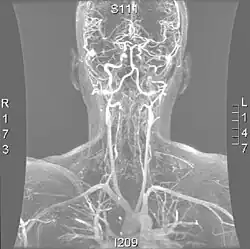

Angio MRI of supra-aortic vessels after the injection of 20cc of gadolinium for contrast

Magnetic resonance imaging has the ability to quantify the plaque anatomy and composition. This allows physicians to determine certain characteristics of the plaque such as how likely it is to break away from the wall and become an embolus. MRI does not use ionizing radiation, so the number of times that it is used on a single person is not a concern; however since it uses strong magnetic fields those who have metal implants cannot use this technique.[1][2]